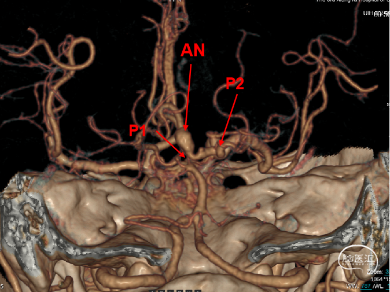

外院CTA示:

1.右侧大脑脚-右侧丘脑急性脑梗死。

2.右侧大脑后动脉P1、2段显影差,P3及其以下未见显影;建议结合临床。

3.结合CTA,符合右侧颈内动脉C7、基底动脉末端动脉瘤。

CT(CTA)检查提示:右颈内动脉C7段大小约3.6×3.8×3.6mm及基底动脉远端动脉瘤形成大小约9.7×7.6×9.3mm。

DSA:右侧P1段一6.8*9.7mm不规则囊状突起动脉瘤,远端P2段呈螺旋状蛇形动脉瘤改变。

DSA:右侧P1段一6.8*9.7mm不规则囊状突起动脉瘤,右侧A1段动脉瘤。夹层蛇形动脉瘤。

DSA:评估右侧后交通。

右侧颈内正位

右侧颈内3D

椎动脉压颈3D